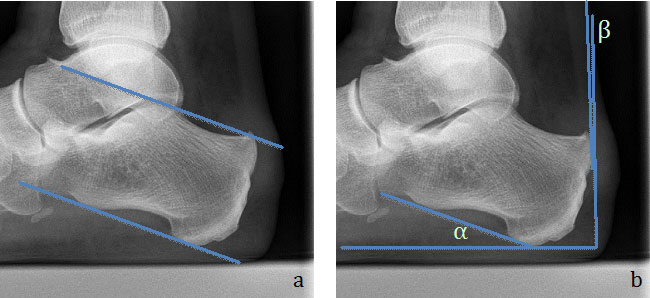

Anhand des seitlichen Fußröntgenbildes kann der Calcaneus-Boden Winkel und die Prominenz der Tuberositas des Calcaneus bestimmt werden und durch das Zusammenspiel dieser beiden Parameter die mögliche Irritation der Achillessehne durch die knöcherne Anatomie beurteilt werden. Bis heute hat sich jedoch kein Parameter etabliert, anhand dessen eine klare Abgrenzung von pathologischen Fehlstellungen möglich ist. Einzelne Arbeiten  zeigen jedoch eine Korrelation der parallel „Pitch-Linien“ und des „Chaveau-Liet“ Winkels  10 zu der Erkrankung (Abb. 2).

a) Die „Parallel pitch lines“ wurden von Pavlov et al. beschrieben. Die untere entspricht dem Calcaneus-Boden-Winkel (Tangente der vorderen zur mittleren Tuberositas). Die obere Linie verläuft parallel zur unteren tangential zum oberen Ende der talaren Fa

Abbildung 2